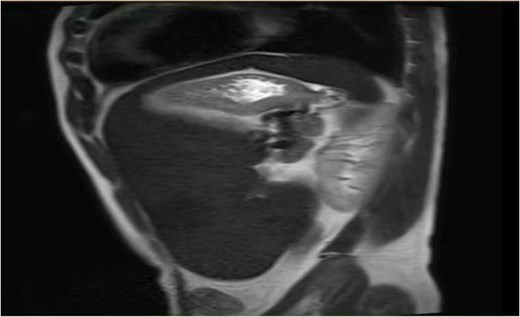

On the 19 August 2024, a 53-year-old man reported to our hospital complaining of “fatigue, jaundice, and abdominal discomfort for 10 years.” His hemolytic jaundice had been present for almost a decade. A family history of hereditary hemolytic jaundice was identified. His daughter and father both experienced similar ailments. Physical evaluation revealed that the skin and sclera were both stained by moderate yellowness. The left abdomen was full, and the spleen was hard and immovable, located 15 cm below the costal border. A computed tomography scan revealed that the spleen was 27.1 cm in length, 7.1 cm in thickness, and located 17.0 cm below the costal border (Figs. 1 and 2). The gallbladder measured 12.0 × 3.2 cm and contained several stones.